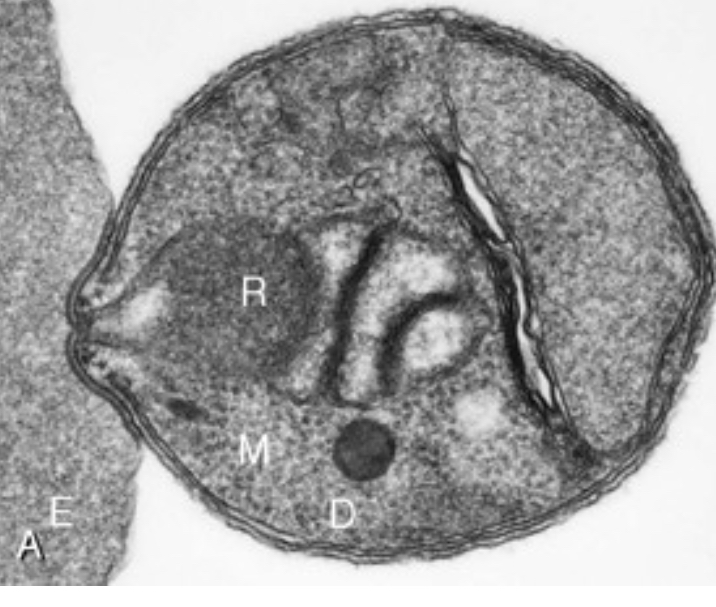

(A) P. knowlesi merozoite invading RBC. (B) P. falciparum trophozoite with hemozoin. (C-D) Knobs and membrane deformation by P. falciparum. (E) Cytoadherence. (F) Rosetting.